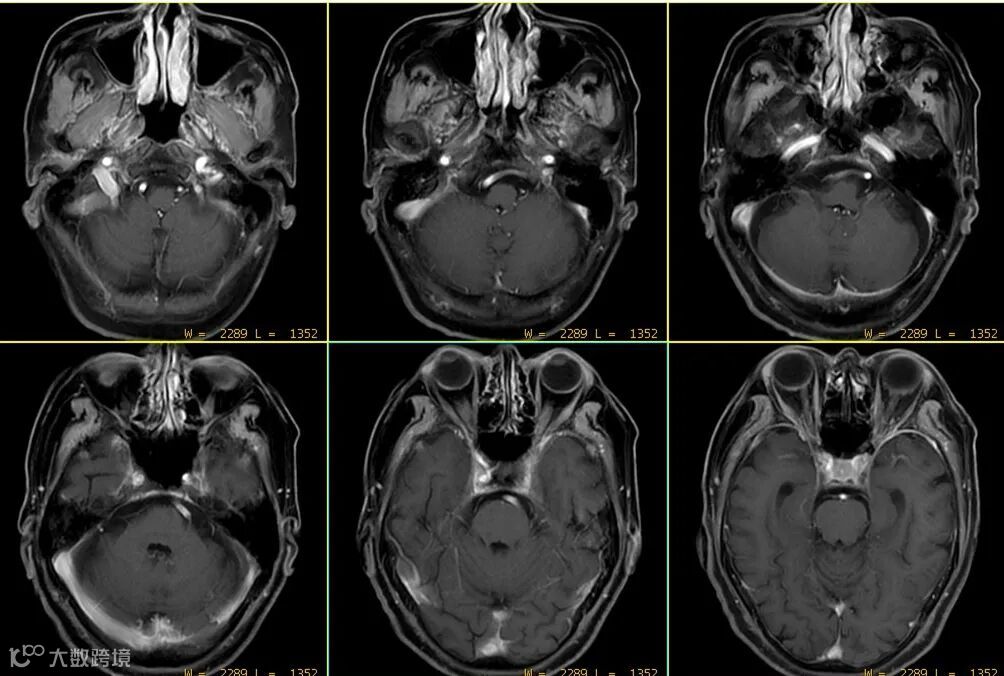

- 但该序列注射对比剂后,横、矢、冠三个方位上血管搏动伪影都非常大,并不利用血管层面及颅底区域病变的显示与判读。如上图△。

- 该序列较2D自旋回波序列,可在一定程度上改善血管搏动伪影。如上图△,该扰相梯度回波T1WI序列上并未见明显血管搏动伪影。